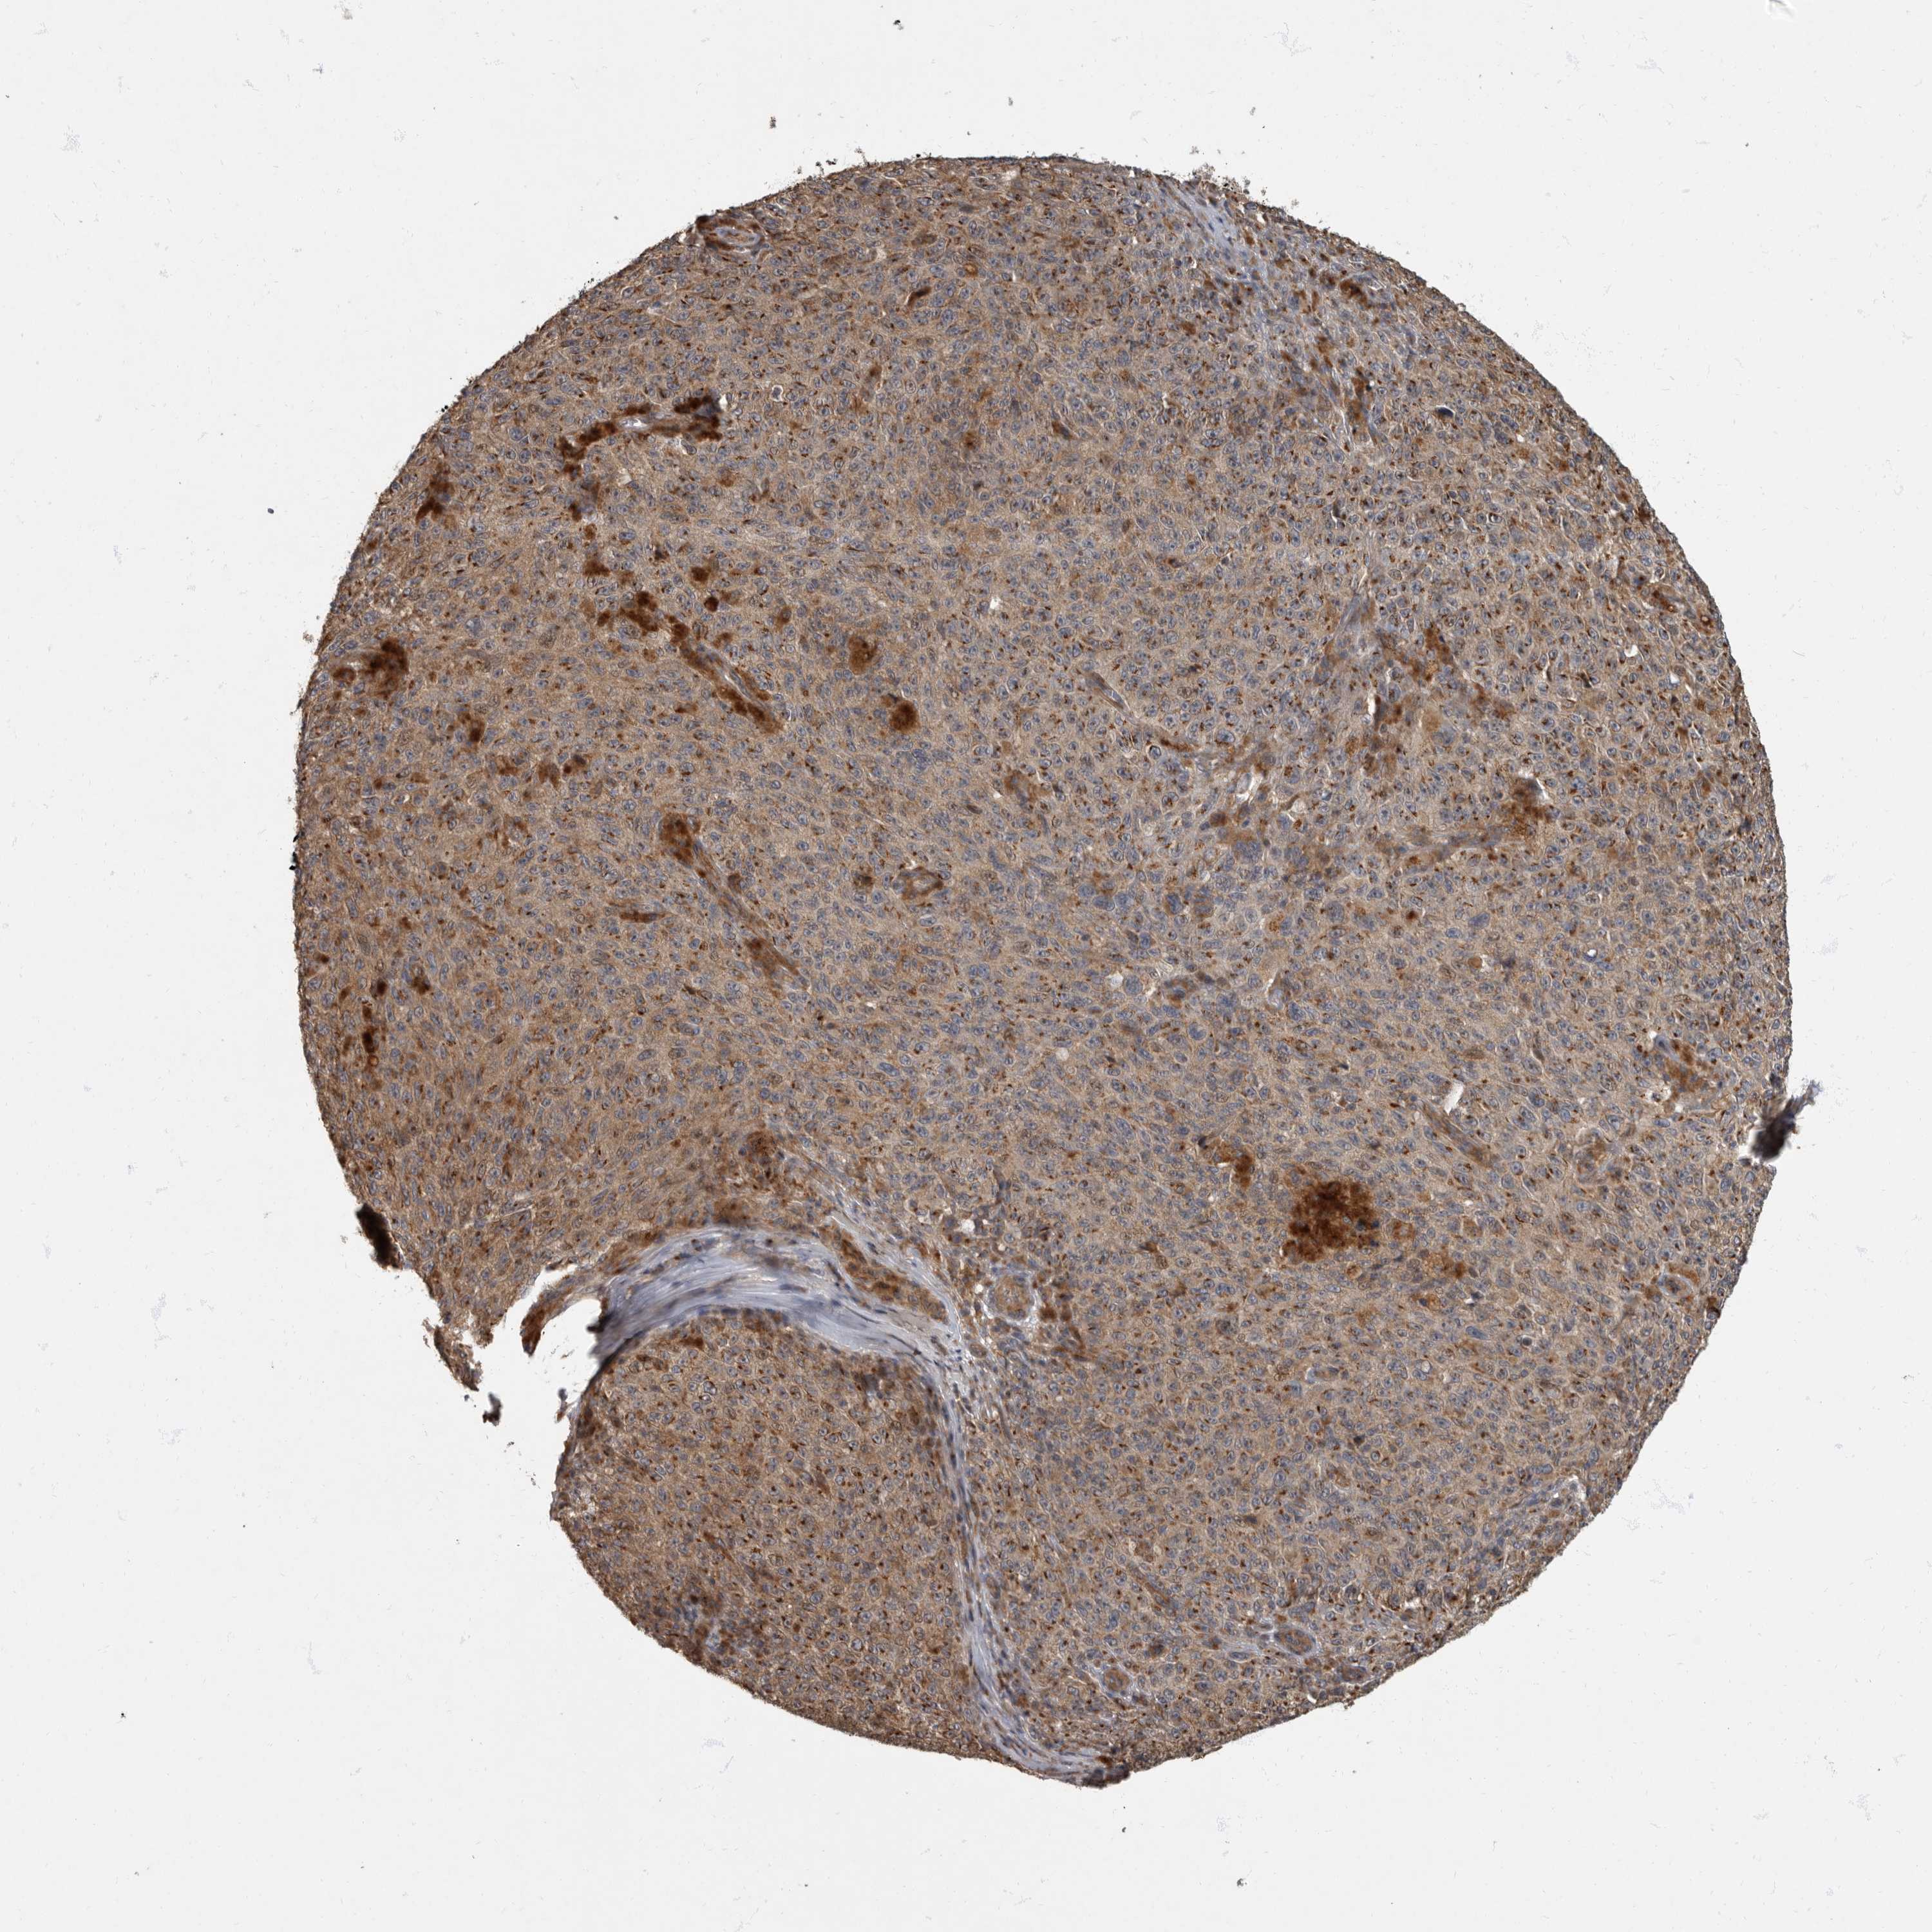

MELANOMA - Protein expressioni

A mouse-over function shows sample information and annotation data. Click on an image to view it in a full screen mode. Samples can be filtered based on level of antibody staining by selecting one or several of the following categories: high, medium, low and not detected. The assay and annotation is described here.

Note that samples used for immunohistochemistry by the Human Protein Atlas do not correspond to samples in the TCGA dataset.

Antibody stainingi

Antibody staining in the annotated cell types in the current human tissue is reported as not detected, low, medium, or high, based on conventional immunohistochemistry profiling in selected tissues. This score is based on the combination of the staining intensity and fraction of stained cells.

Each image is clickable and will lead to virtual microscopy that enables deeper exploration of all samples and also displays staining intensity scores, fraction scores and subcellular localization as well as patient and tissue information for each sample.

Antibody HPA026792

Staining

High

Medium

Low

Not detected

Intensity

Strong

Moderate

Weak

Negative

Quantity

>75%

75%-25%

<25%

None

Location

Nuclear

Cytoplasmic/membranous

Cytoplasmic/membranous,nuclear

Malignant melanoma, NOS

Malignant melanoma, Metastatic site